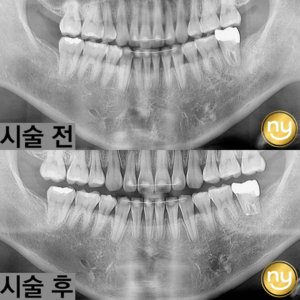

울산안아픈치과 신경치료 후 염증 치아재식술로 해결해요! 안녕하세요. 울산안아픈치과 뉴욕연합치과입니다. 임플란트가 워낙 보편화되고 선호하는 분들이 많아지고 있지만, 자연치아를 살리고자 하는 수요도 급상승하고 있는 추세입니다. 위 환자분은 충치가 많이 진행되어 신경치료한 치아를 사용하고 있었습니다. 하지만, 오랜 기간이 지나 치아 뿌리 끝에 염증이 생겨 발치를 권유받았는데요, 발치를 하더라도 치아 뿌리만 손상 더보기…